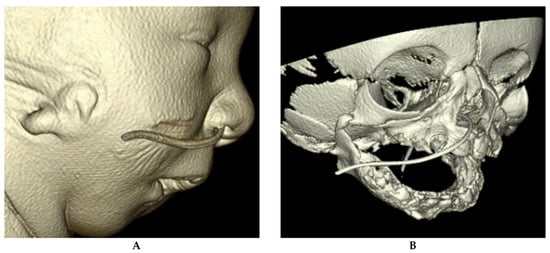

2.12.1. Congenital Nasal Pyriform Aperture Stenosis